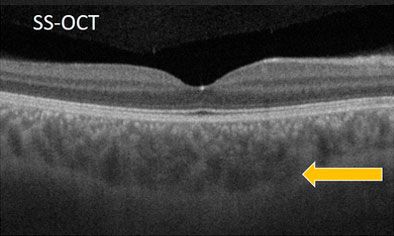

При SD-OCT хориоидея визуализируется слабо — размыты границы, особенно в глубоких слоях. При SS-OCT сосудистая оболочка чётко прослеживается по всей толщине до склеры благодаря высокой проникающей способности инфракрасного лазера.